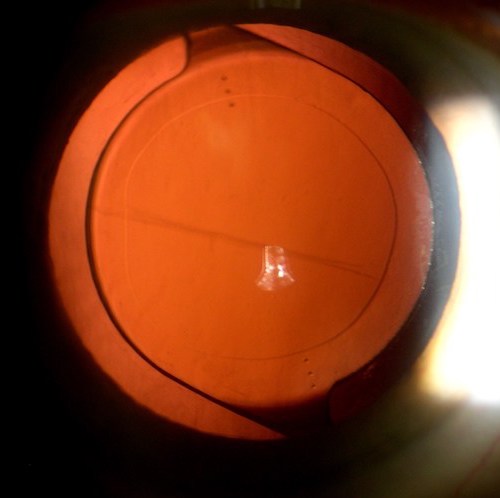

onpit

Posterior Segment & Retina

1. Fahim, NM, Sharma M Anatomical Explanation of Optic Disc Pit Maculopathy Associated with Good Visual Acuity Poster Presentation at Annual Optometry’s Meeting 2017 at Washington, DC.